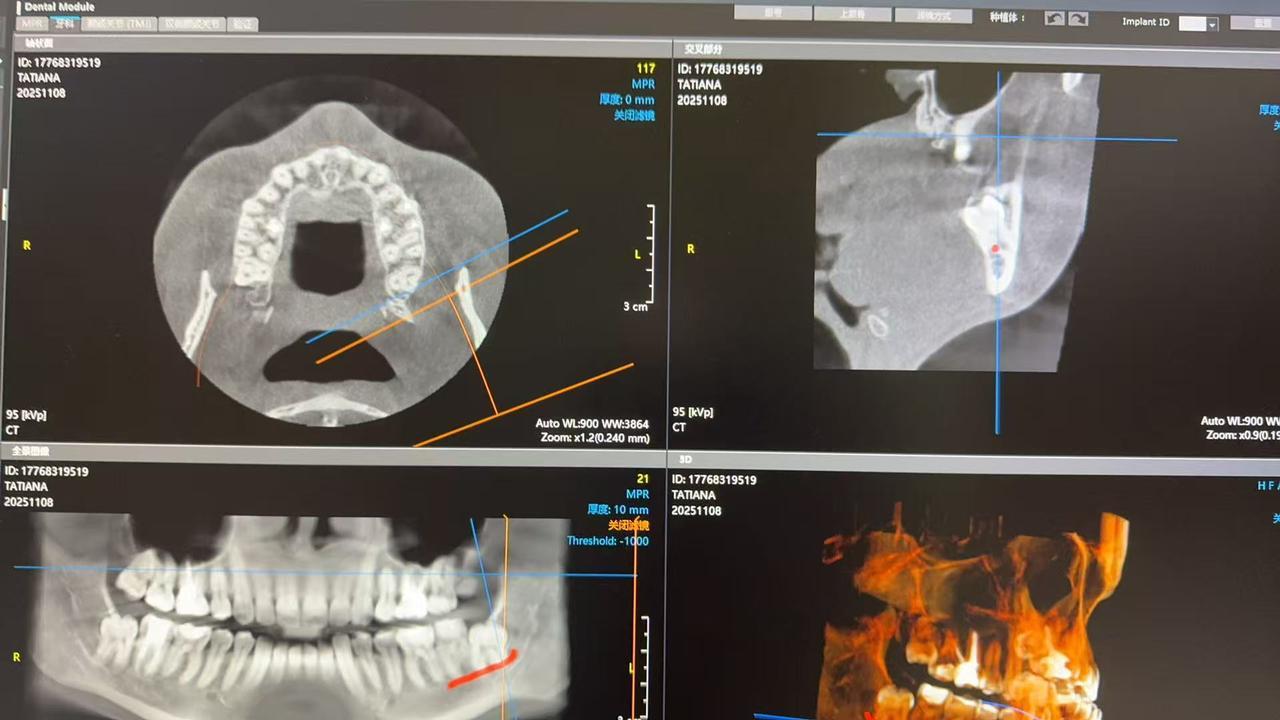

Ситуация:

Нижние зубы затрагивают лицевой нерв, говорят нельзя удалять, но они давят и начинают искривлять остальные зубы, над ними еще челюстная кость, наверх не могут прорасти. Пока думаю несколько вариантов, либо удалить соседние, либо отпилить часть кости, установить винты и ждать 3-6 месяцев когда вырастут, потом удалять, когда отойдут от нервов или найти челюстно-лицевого хирурга, но 100% гарантии, что нервы не затронут не дают. Поэтому я все еще в поисках специалиста и более безопасного решения 😅

КТ ПРИКРЕПЛЯЮ